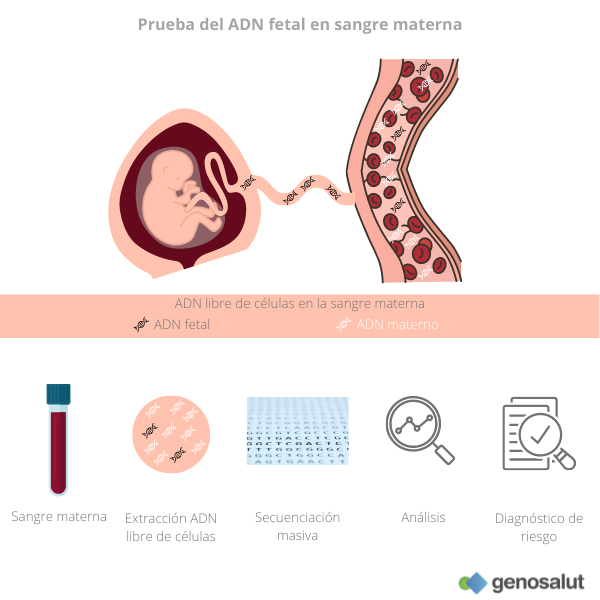

An lisis ADN fetal en sangre materna Genosalut